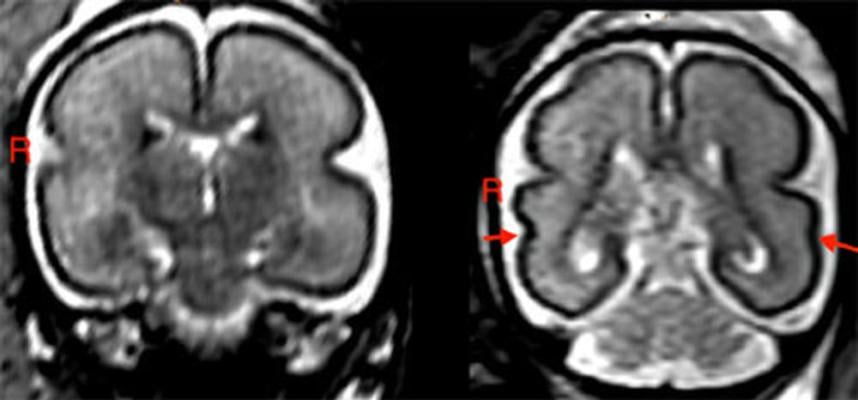

In fetuses with alcohol exposure, the fetal total maturation score (fTMS) was significantly lower than in the age-matched controls, and the right superior temporal sulcus (STS) was shallower. The STS is involved in social cognition, audiovisual integration and language perception.

"We found the greatest changes in the temporal brain region and STS," Dr. Kasprian said. "We know that this region, and specifically the formation of the STS, has a great influence on language development during childhood."

According to the researchers, delayed fetal brain development could be specifically related to a delayed stage of myelination and less distinct gyrification in the frontal and occipital lobes.

Gyrification refers to the formation of the folds of the cerebral cortex. This folding enlarges the surface area of the cortex with limited space in the skull, enabling an increase in cognitive performance. When gyrification is diminished, functionality is reduced.